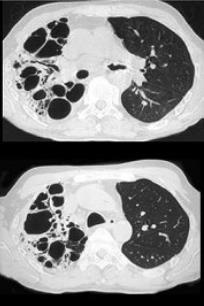

男,31岁,反复咳嗽,咯血10年余,结合影像学检查,最可能的诊断是()。

A:肺囊肿

B:间质性肺炎

C:肺曲菌病

D:支气管扩张

E:肺结核